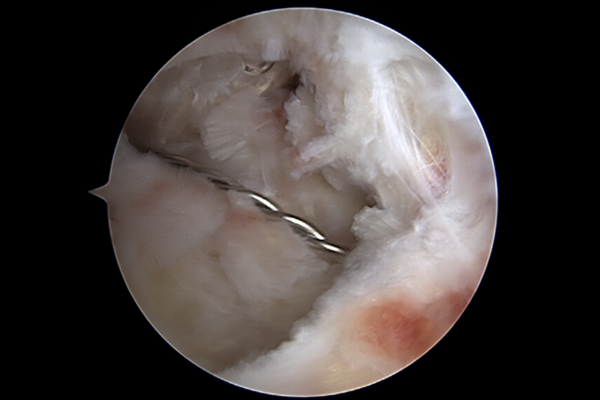

정확한 무릎 상태를 파악하기 위해서 촬영한 MRI 결과, 후방십자인대가 파열된 것이 확인되어 무릎 후방십자인대 파열(Posterior cruciate ligament rupture knee)을 진단하였습니다.

환자분께 현재 후방십자인대 파열 정도가 심하기 때문에 수술적 치료가 필요하다는 사실과 수술의 방향성을 설명드리고, 최소침습 관절경하 후방십자인대 재건술(A/S Posterior cruciate lagament[PCL] reconstruction)을 시행하였습니다.